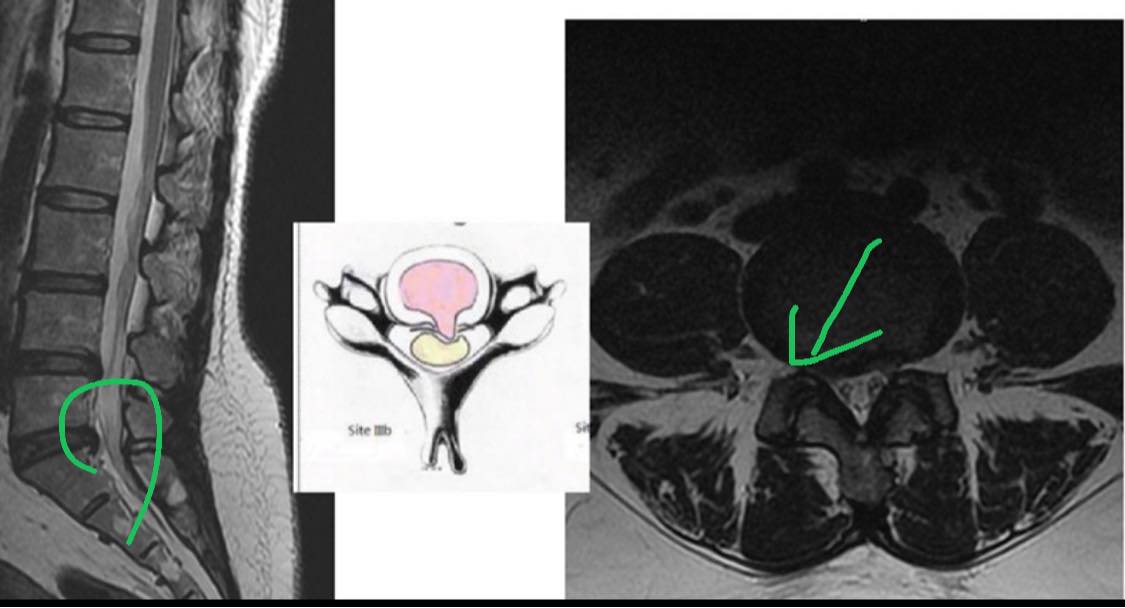

診斷:L4/L5;L5/S1 椎間盤突出

3.椎管側隱窩減壓術